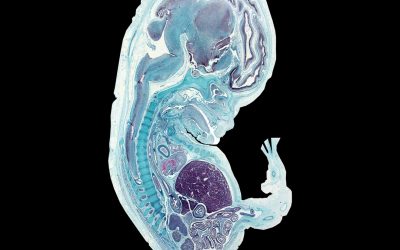

Surgical Embryology

A grounding in anatomical embryogenesis should in many ways be the foundation of your anatomical study. It gives insight and understanding to the form, location and relationship of structures, and explains much of the variations and pathology encountered as a surgeon....